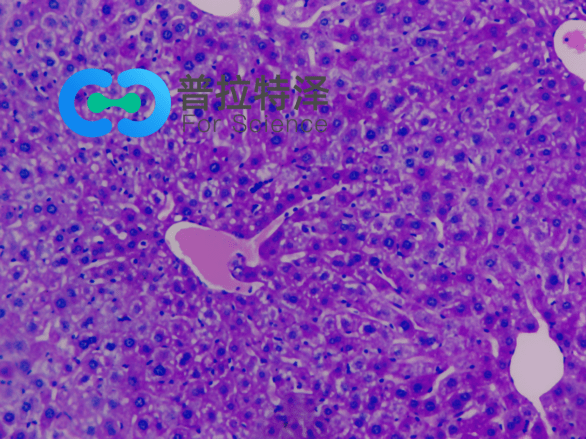

在生物學(xué)和醫(yī)學(xué)領(lǐng)域,PAS染色(Periodic Acid-Schiff Stain)是一種常用的組織染色技術(shù),用于檢測組織中的多糖類物質(zhì),如糖原和粘多糖。掌握PAS染色的正確步驟,對于科研人員和醫(yī)學(xué)工作者來說至關(guān)重要。普拉特澤生物——組織染色實驗平臺操作各類組織的染色實驗上百例,專業(yè)代做PAS染色和各種染色實驗,本文將從入門到精通,全面介紹PAS染色的步驟和注意事項。

→Schiff試劑染色:將氧化后的切片放入Schiff試劑中,醛基與Schiff試劑中的亞甲基藍發(fā)生反應(yīng),形成紫紅色產(chǎn)物。

→蘇木精復(fù)染:用蘇木精對切片進行復(fù)染,使細(xì)胞核呈現(xiàn)藍色。